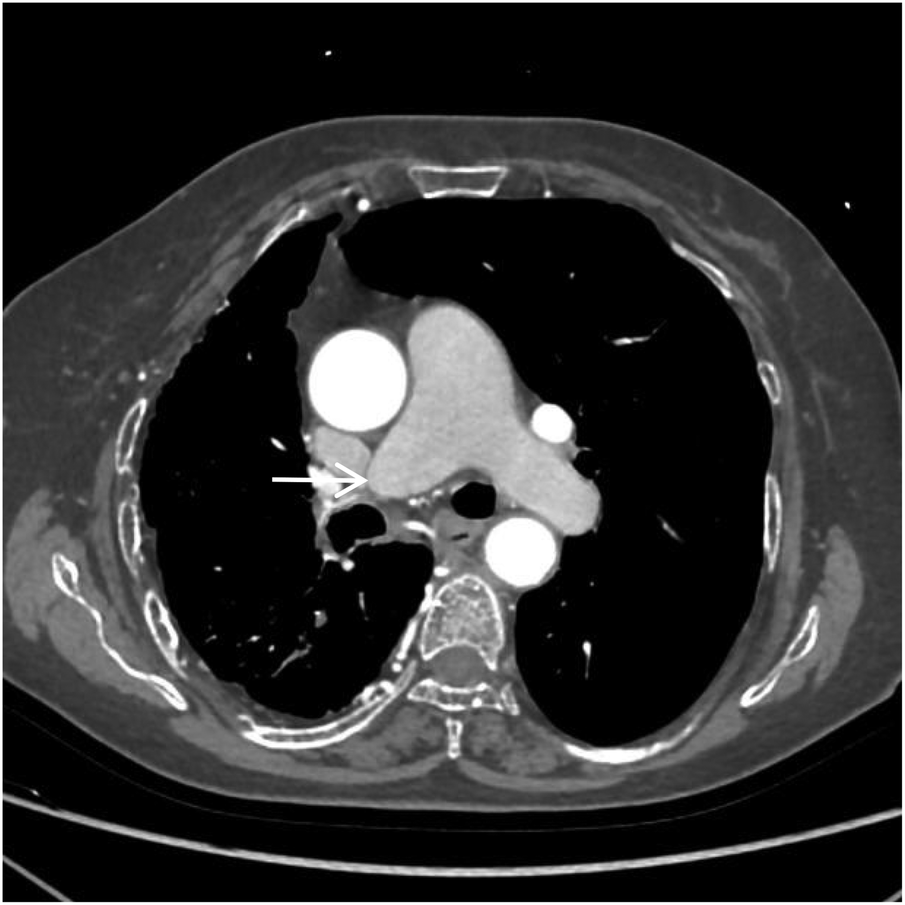

Figure 1

VR image shows absence of the distal main right pulmonary artery, with a rounded and blunt stump (white arrow).

Figure 2

CTA axial image shows absence of the distal right pulmonary artery, with a rounded and blunt stump (white arrow). No abnormal density shadows are observed within the main pulmonary artery and the proximal segments of the left and right pulmonary arteries.